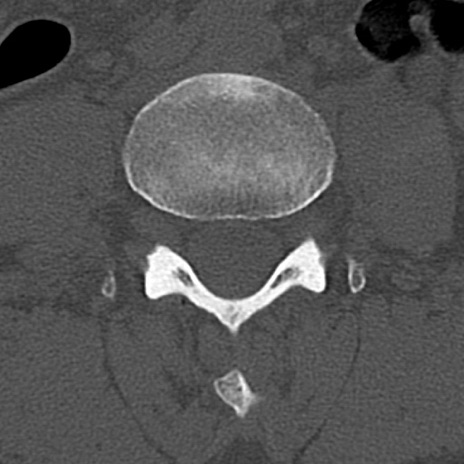

【整形】TIPS症例4 腰椎CT(横断像)

腰椎CT

横断像と矢状断像